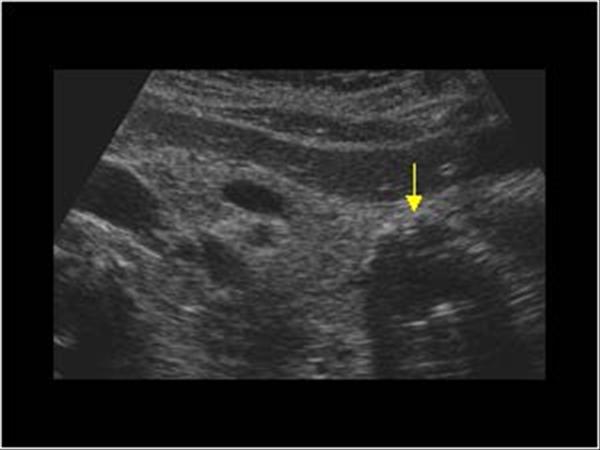

4. kép:

Hasnyálmirigy pseudocysta

Ez az eltérés akut hasnyálmirigy gyulladást követően alakulhat ki. Ezen a képen a farok régióban figyelhető meg a pseudocysta, melyet a sárga nyíl jelez. A falában meszesedések is láthatóak, amit a világos foltok, illetve a cysta mögötti hangárnyék is jelez.